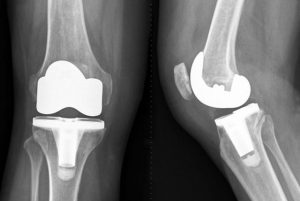

人工膝关节由金属和聚乙烯构成,置换手术也并非切掉整块骨头,而是用人工假体置换关节的表面,有些像戴个牙套,也可以根据病情,进行全膝关节置换和部分膝关节置换。这种手术的目的在于缓解疼痛,提高生活质量,改善膝关节功能。原则上适合所有年龄段的人,但由于人工关节有使用寿命,中老年患者进行置换得较多。医生也可能建议一些年轻患者推迟手术。

进入麻醉后,开始手术,手术时间在1到2.5个小时,和医生的熟练程度关系很大,手术后患者可能会接受数小时的监控,直到麻醉效果消失。此后患者会在医院住几个晚上,有些患者可以在第三天出院。